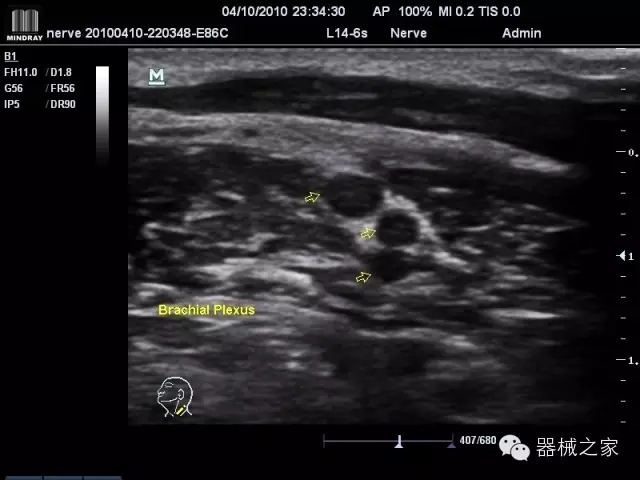

·優(yōu)秀的圖像效果、強(qiáng)大的功能體驗(yàn)、豐富的探頭選擇、合理的便攜式設(shè)計(jì),全中文顯示及病人管理界面,使得M7在任何場(chǎng)合、任何時(shí)候都能快速響應(yīng)更好的心血管、腹部、婦產(chǎn)、小器官等常規(guī)超聲檢查以及肌骨、神經(jīng)、顱腦、術(shù)中等新興領(lǐng)域的使用需求;